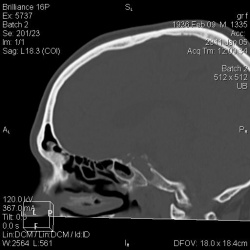

Девочка 13 лет, поступила с подозрением на ЗЧМТ. Случайной находкой было обнаружение деформация спинки Турецкого седла. Пересмотрев норму и варианты, подходящего седла не нашел. Может...